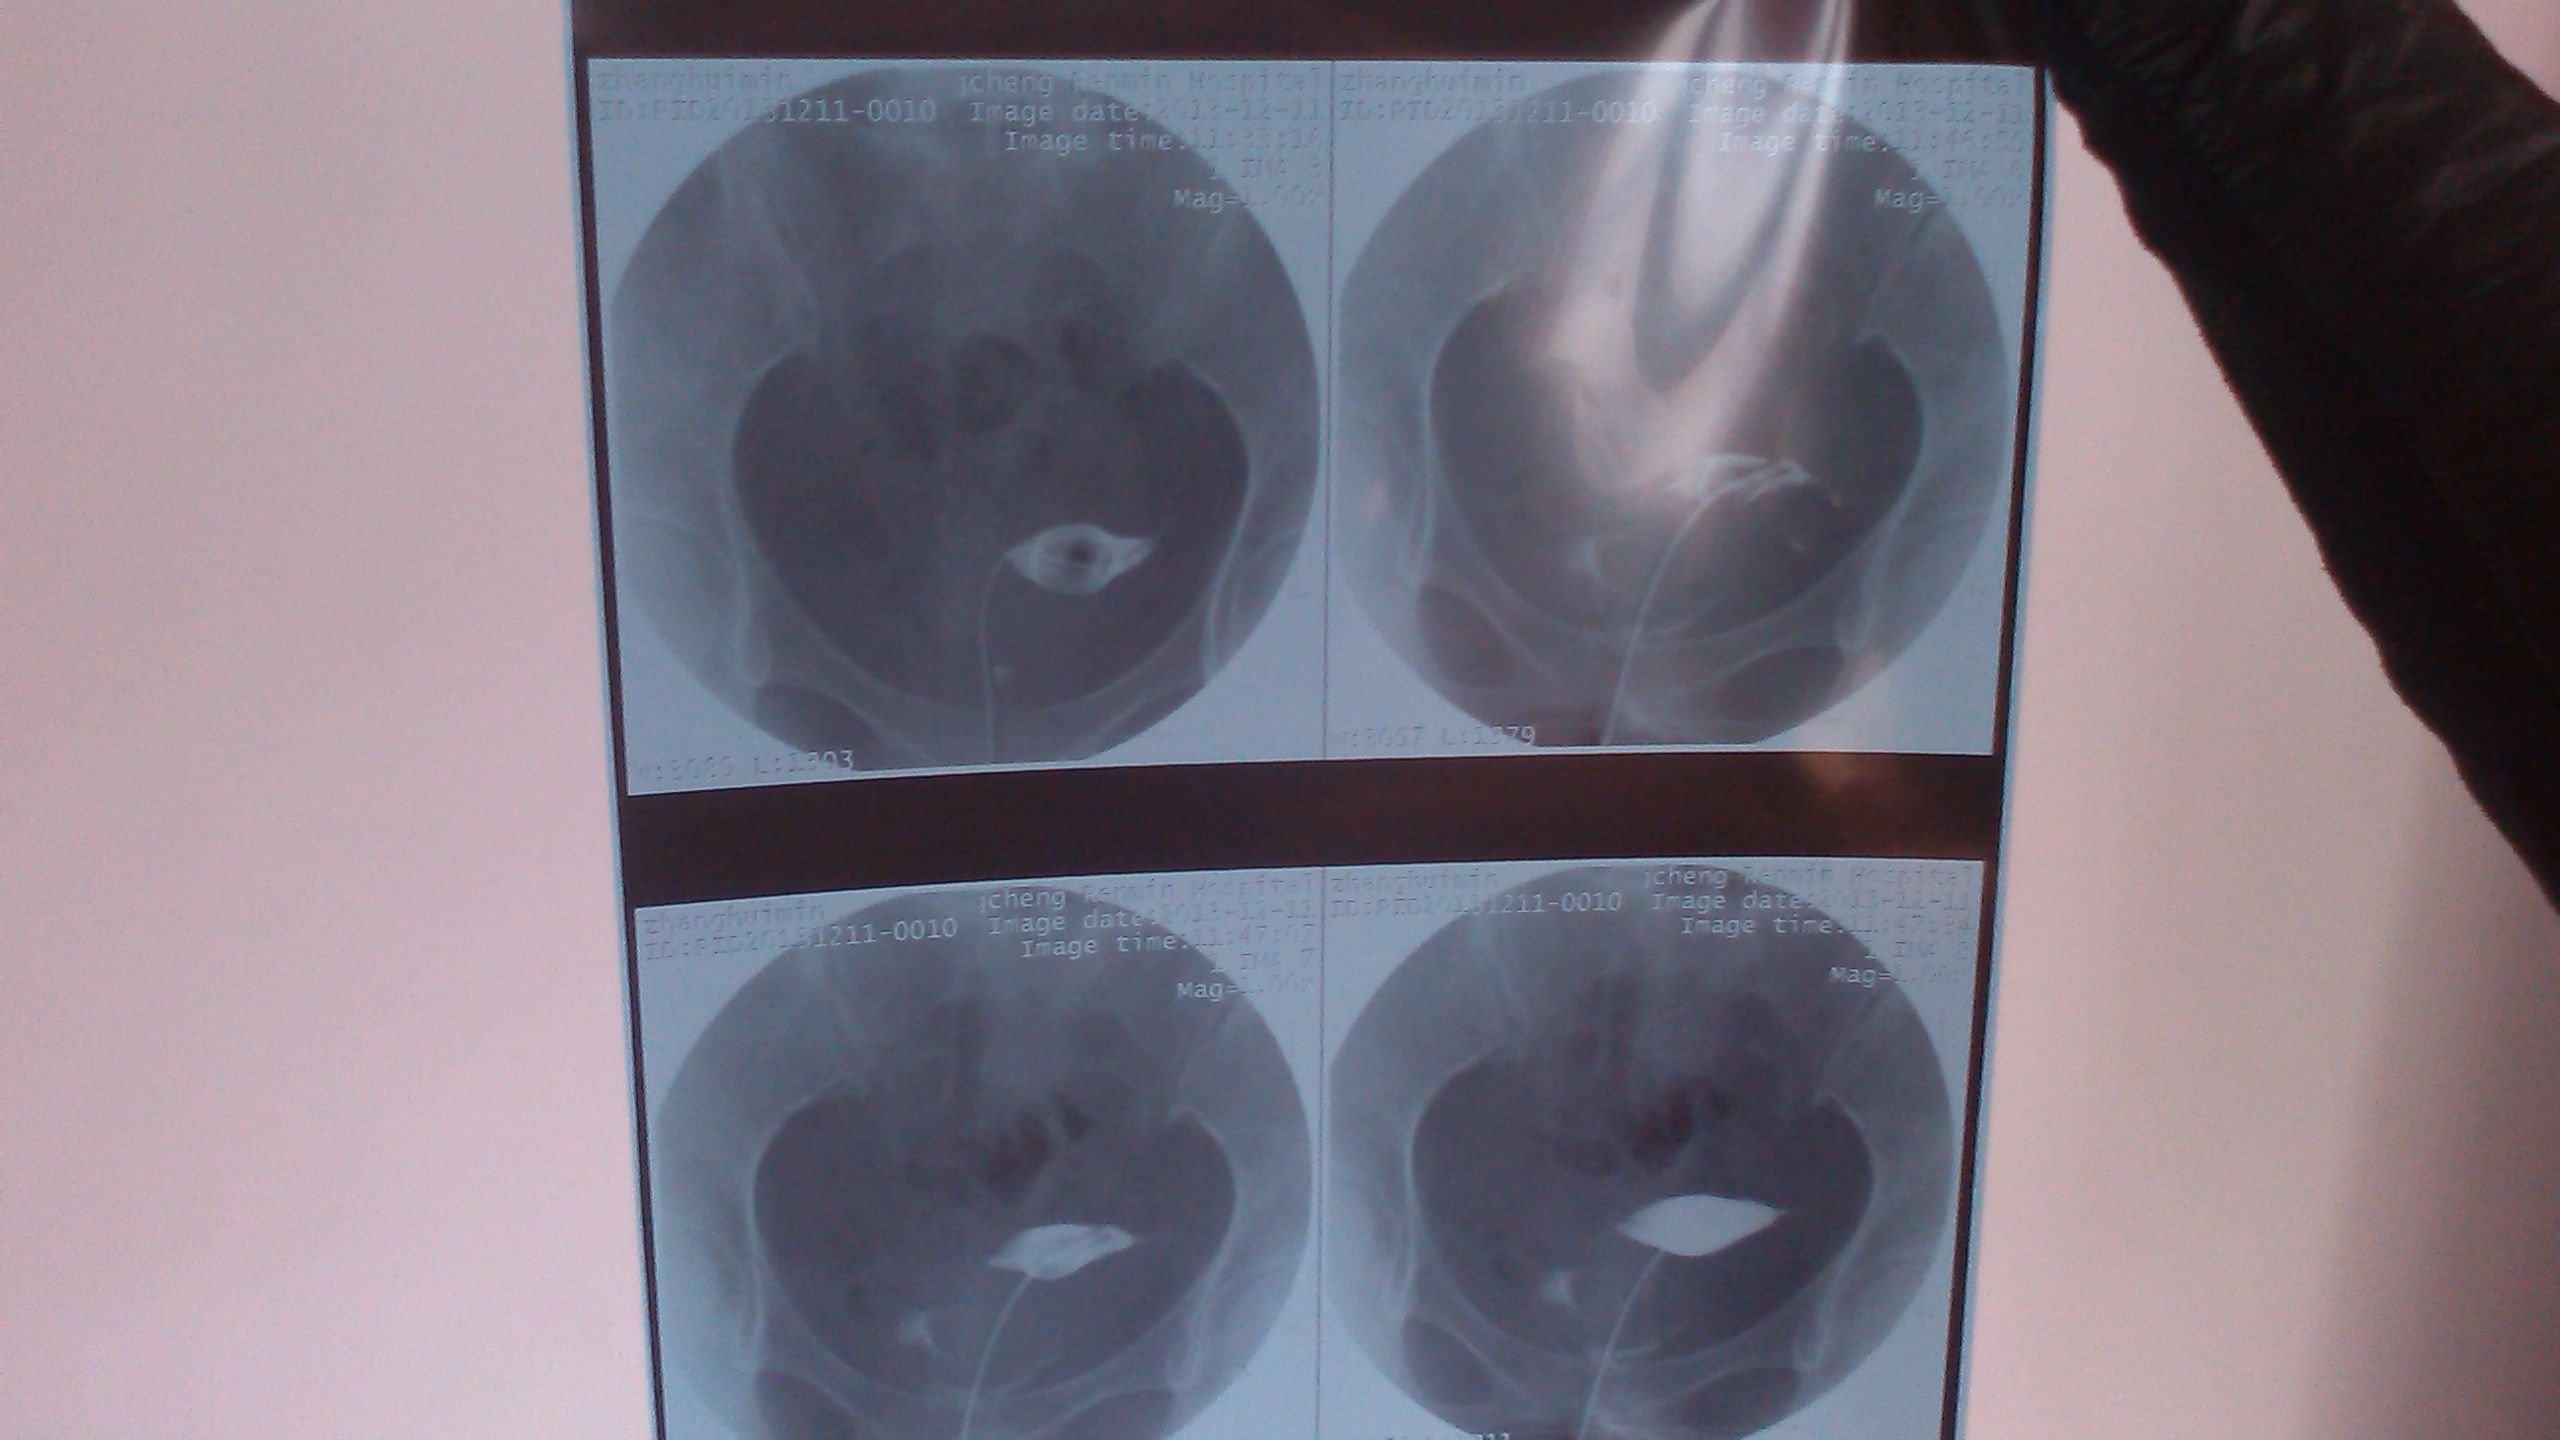

子宫宫腔呈三角形,内壁光滑,整齐,大小正常,造影剂显示至双侧子宫角,输卵管辖部见少量显影,余输卵管